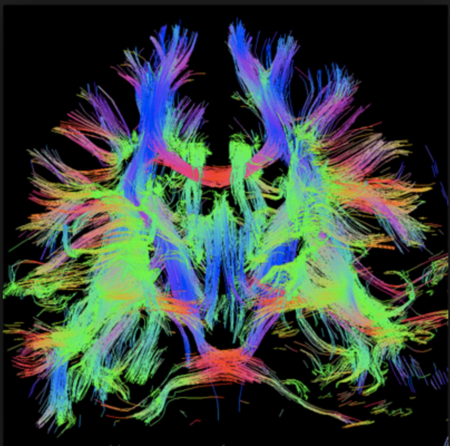

For at retningsbestemme skal DTI undersøgelsen foregå i mindst 6 forskellige retning, derefter anvendes 3D Gaussisk sandsynlighedsberegning til bestemmelse af 3x3 matriks som kaldes en diffusion tensor. En diffusion tensor er karakteriseret ved en eigen value og en eigen vector og kan man matematisk bestemme retningen af bevægelse. FA (fractional anisotropi) angiver graden af anisotropi med en FA-værdi på 0 sv.t. komplet isotopi = helt tilfældig bevægelse, til FA=1 sv.t. komplet anisotropi med udelukkende bevægelse i en retning. I en visuel fremstilling af retning vil en FA-værdig på = svarer til en kugle (en cirkel i planet) mens en FA-værdi på 1 vil svarer til en linje. FA=1 findes ikke i biologisk væv og de vil i stedet have ellipse form.

DTT fremstilles ved at tegner baner gennem eigen vektors i tilstødende voxels, man sætter typisk grænser for skarpt en "tract" mål dreje og minimums længde af de baner der skal findes.